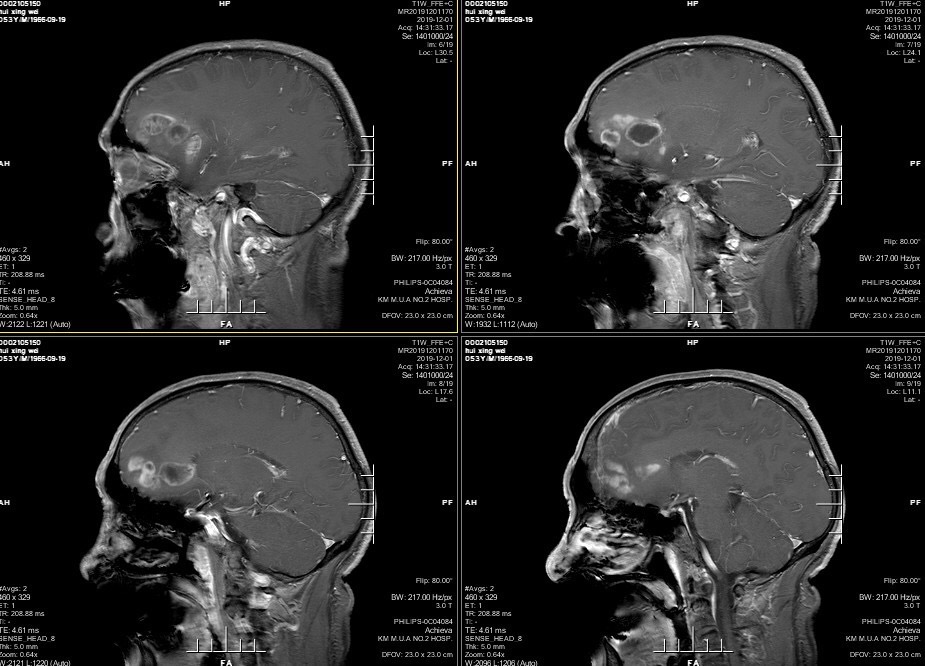

男性患者,53岁,主诉:反复头痛伴恶心一周,突发意识丧失一次。入院查体:神经体统无阳性体征。入院头颅MRI:左额叶胼胝体区囊实性占位,不均匀强化,考虑高级别胶质瘤;长程视频脑电监测提示左侧中央区、顶区、后颞区见中等量低-中-高波幅痫样放电。术前诊断:1.左额叶胼胝体区占位病变;2.继发性癫痫,入院给予降颅压及抗癫痫处理,积极完善术前准备后于2019年12月3日全麻下完成手术,术中行B超引导下切除肿瘤。术后患者无肢体功能及语言功能障碍,复查头颅核磁肿瘤全切,一周后出院开始放化疗治疗。

肿瘤为囊实性。

双侧大脑前动脉受肿瘤推挤。

增强后不均匀强化。